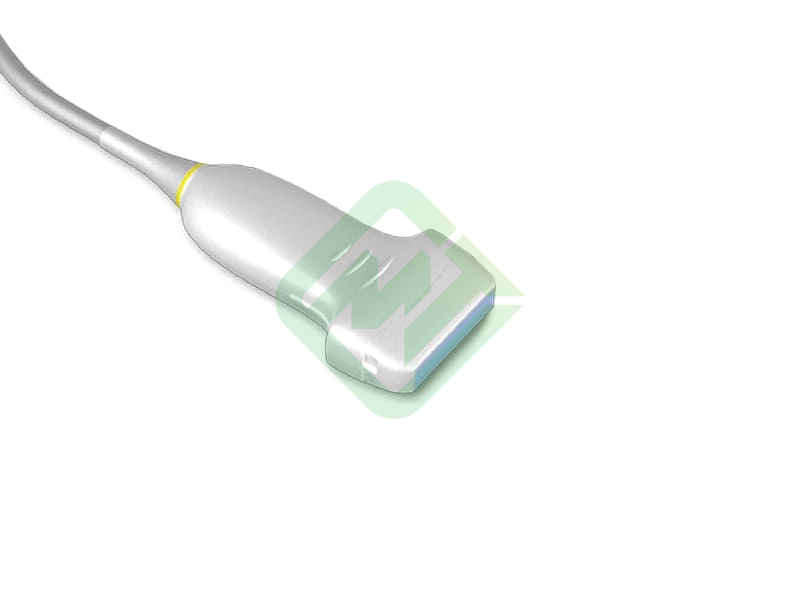

— мультичастотные УЗ-датчики: линейный датчик Edan L742UB, конвексный датчик Edan C352UB, фазированный датчик Edan P5-1b

— линейным L742UB: частотный диапазон датчика 5–10 МГц, апертура 40 мм, глубина сканирования 130 мм, количество элементов 128

- Датчик линейный ультразвуковой L742UB — 1 шт.